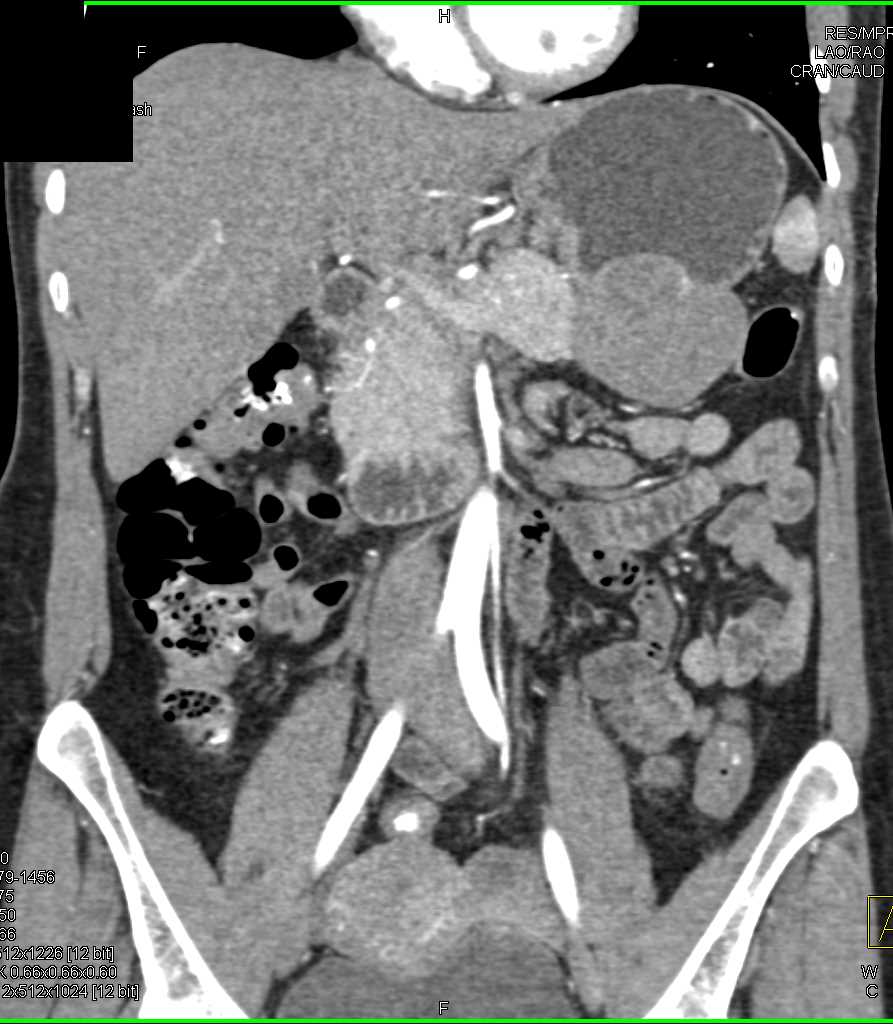

Mass Pushes on Tail of Pancreas was Ganglioneuroma